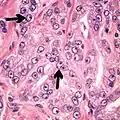

- Relatively common and highly specific

- [4]

- Multiple nucleoli

- Eccentric nucleoli[4]

-

Acinar adenocarcinoma with multiple nucleoli.

Acinar adenocarcinoma with multiple nucleoli. -

Acinar adenocarcinoma with double and eccentric nucleoli.

Acinar adenocarcinoma with double and eccentric nucleoli.